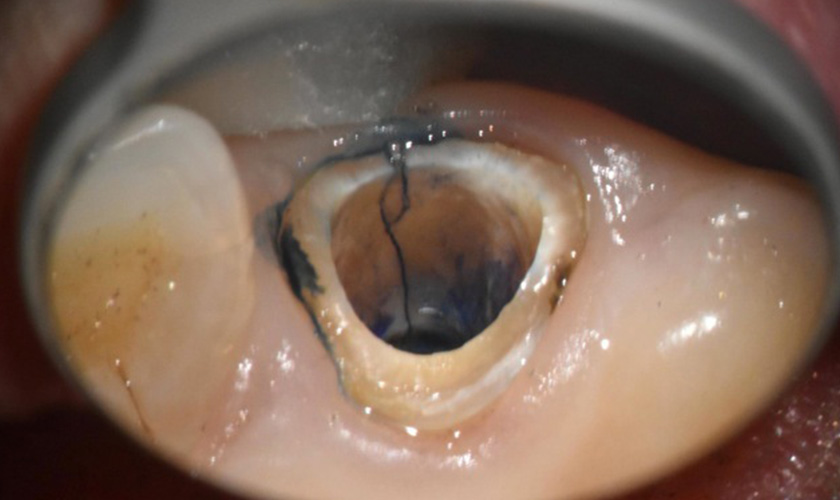

治療途中

左のX線の矢印で示してある歯が割れていたので、一旦歯を抜いてきれいにしました。

修復後

きれいにした後に、修復をして元に戻しました。